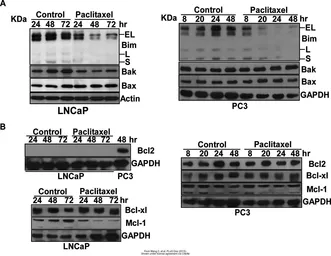

The data was published in the journal Cell Div in 2019. PMID: 31110557